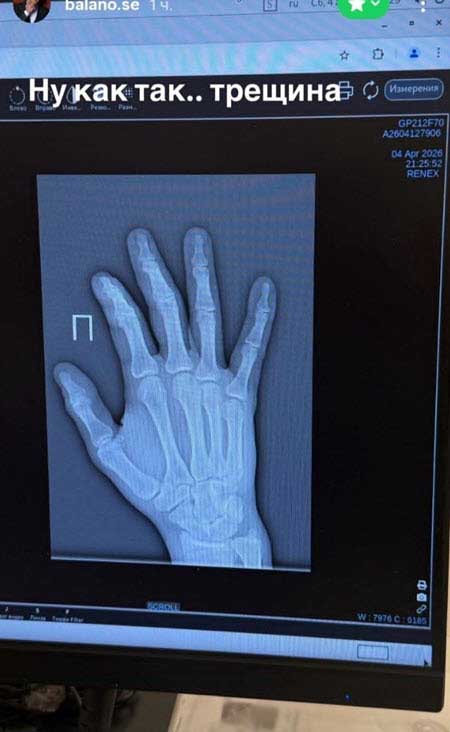

Участник проекта Владимир Балан был вынужден обратиться в травмпункт, парень повредил руку. В больницу Владимира отвезла его проектная девушка Нонна Щукина, Балану наложили гипс на руку, рентген показал трещину. В сторис Владимир рассказал, что продолжает ходить в спортзал и не останавливает тренировки, несмотря на травмы. Неудачи преследуют спортсмена, недавно Балан получил серьезную травму колена и колено у него все еще болит, теперь проблемы с рукой.